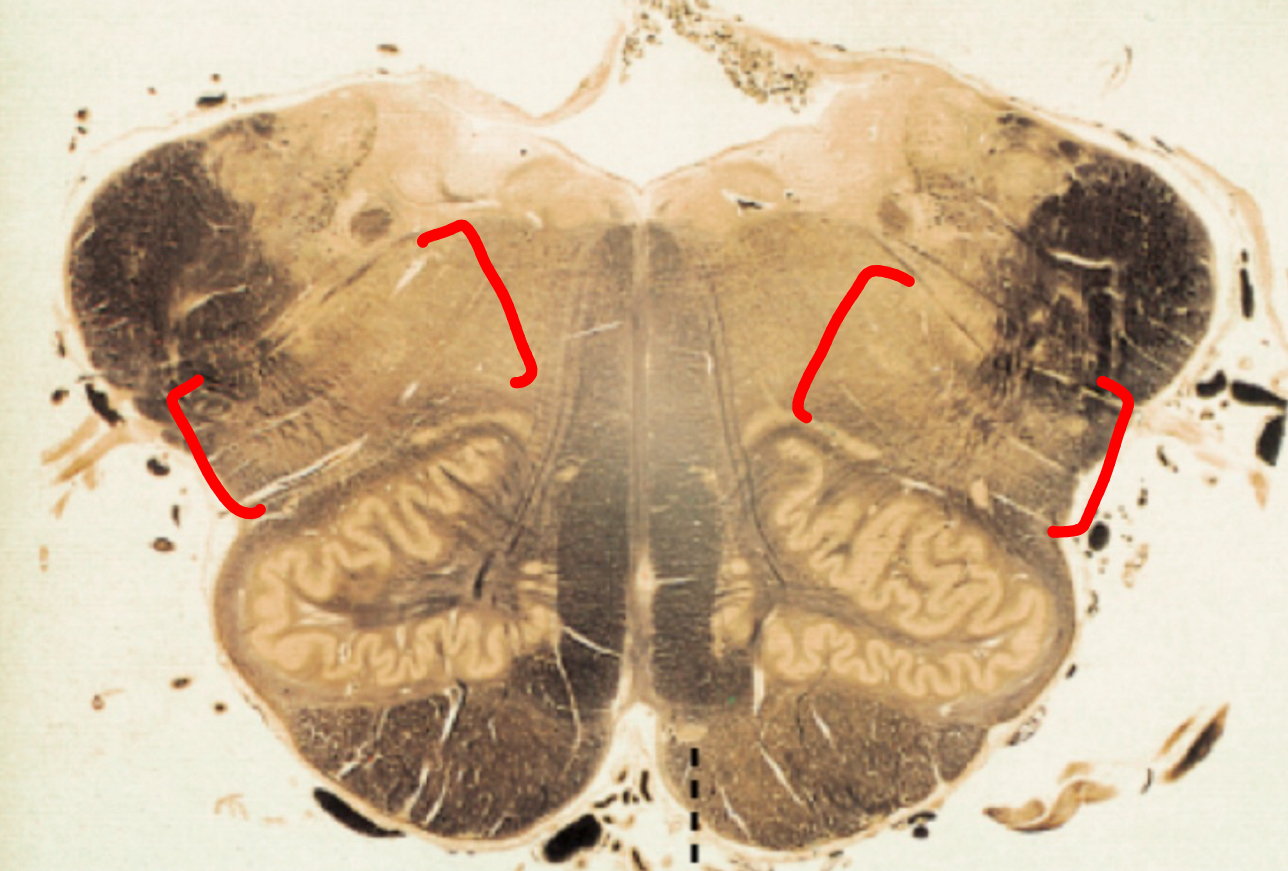

cerebellar peduncles